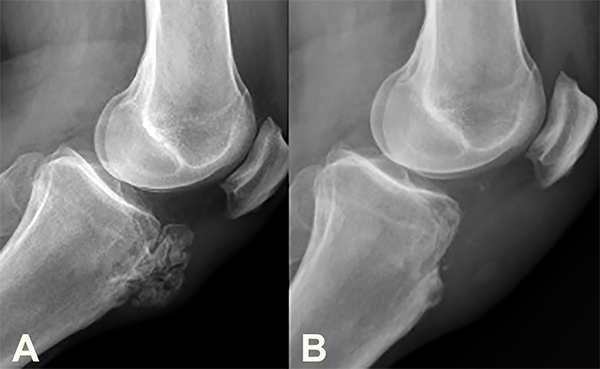

En las radiografías (Rx) se observó una tumoración vellosa con múltiples calcificaciones sobre la TAT, edema y engrosamiento del tendón rotuliano (TR). Se advirtió, además, una imagen esclerosa medular de bordes netos en la región metafiso-diafisaria distal del fémur (fig. 2).

Figura 2: Radiografía de frente (2a) y perfil (2b). Véase la tumoración a nivel anterior de la TAT con múltiples calcificaciones. Imagen en canal medular del fémur con bordes escleróticos.